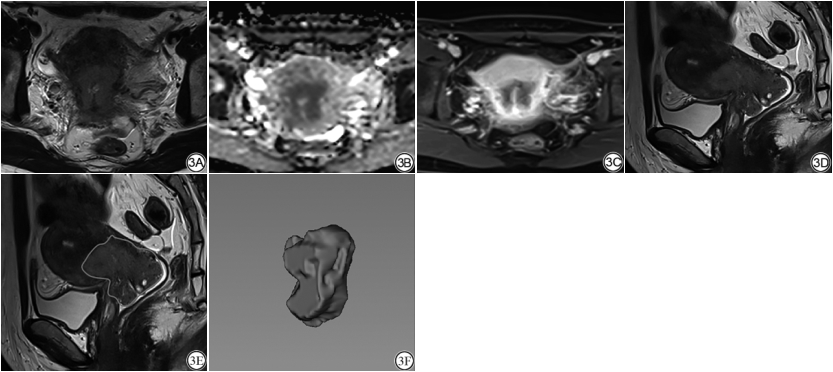

本研究结果较好,原因之一为本研究中的两位观察者具有丰富的影像诊断经验,对肿瘤的分割一致性较高。而且本研究将病理分型及分级纳入模型,并且将临床及病理特征进行了筛选,筛选出的3个临床特征即月经状态、癌症家族史、病理类型较9个临床特征较易获得且准确,进而使得模型分类准确率、敏感度、特异度明显提高。动态增强扫描采用不同的模型其诊断效能不尽相同[21, 22],目前缺乏统一的标准,故本研究采用常规增强进行建模,进入模型的四个磁共振序列重复性强且稳定,且在模型过程中增加了防止过拟合操作。因此本研究构建的神经网络模型分类准确率较高,更易推广,如图3。